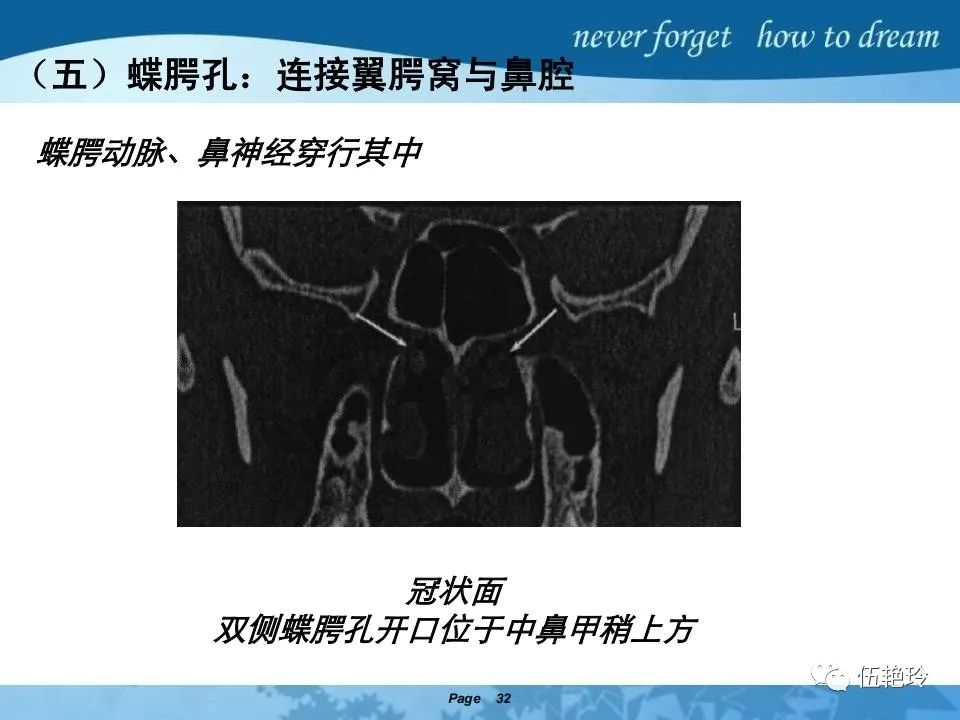

2.31 向上颅内:①鼻咽顶壁→破裂孔(岩尖、斜坡)→蝶窦、海绵窦;②鼻咽顶壁→蝶骨基底部→蝶窦、海绵窦;③鼻咽侧壁→茎突前间隙→蝶骨大翼(卵圆孔)→海绵窦;④鼻咽侧壁→茎突前间隙→翼腭窝→ 颞下窝;⑤鼻咽前壁→鼻腔→翼突、翼腭窝→眶下裂→眶尖→海绵窦;⑥鼻咽前壁→鼻腔→上颌窦、筛窦;